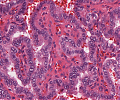

A70 Adenokarzinom des Kolon

Tumordrüsen mit deutlicher Kernpleomorphie

A70 Adenokarzinom des Kolon

Klein- und großdrüsige Tumordifferenzierung an der Invasionsfront